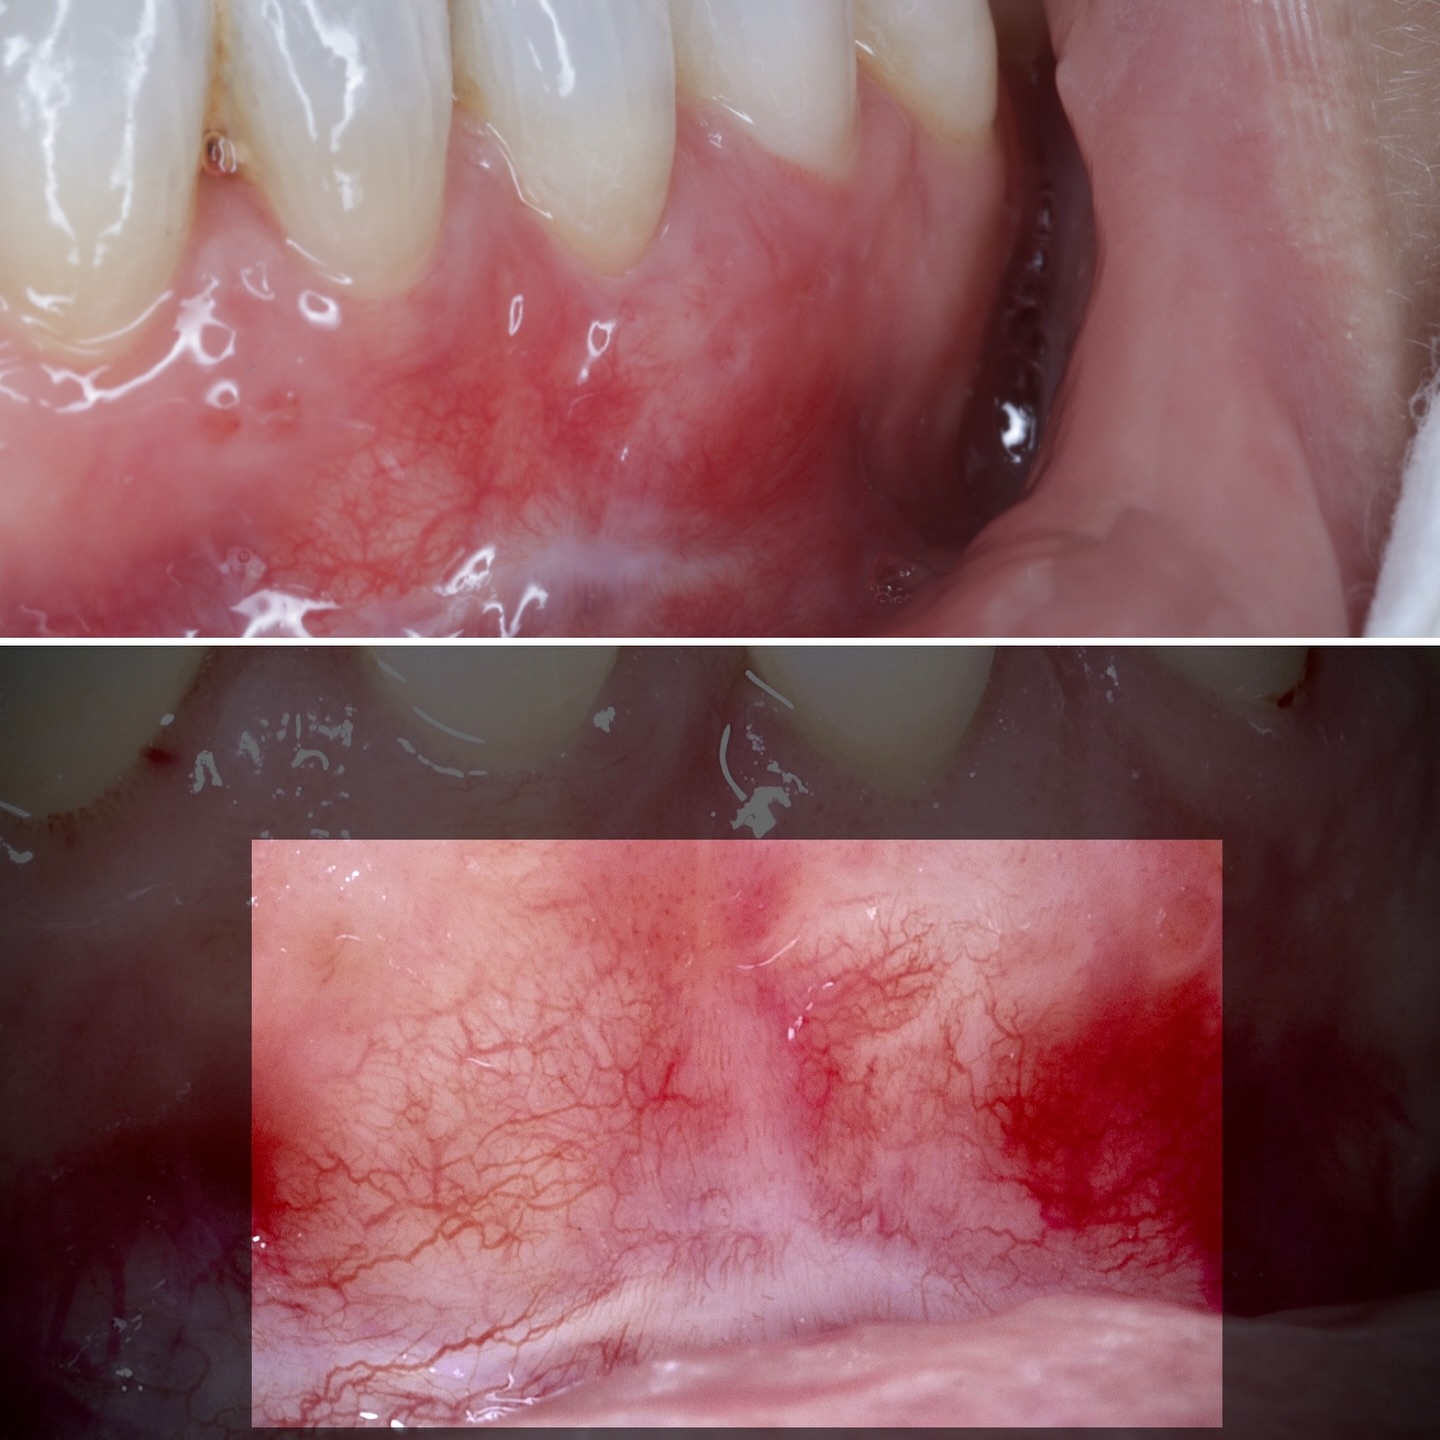

Durante una mañana, asistirás a una Cirugía Mucogingival de recubrimiento radicular de recesiones múltiples en IV y V sextante (36 a 43).

Aprende la planificación y técnica de la cirugía Mucogingival para el recubrimiento de recesiones y aumento de banda queratinizada en el sector anteroinferior

La formación comenzará con la presentación del caso clínico que se abordará durante el curso, seguida de una cirugía en directo, que permitirá observar paso a paso el procedimiento y la toma de decisiones clínicas. Durante la jornada se profundizará en los conceptos biológicos aplicados a

Formación teórico-práctica completa sobre las técnicas más avanzadas en cirugía mucogingival. Durante dos días intensivos, los participantes aprenderán desde la evidencia científica y la anatomía de las zonas donantes hasta la ejecución de injertos, cubrimiento radicular y aumento de